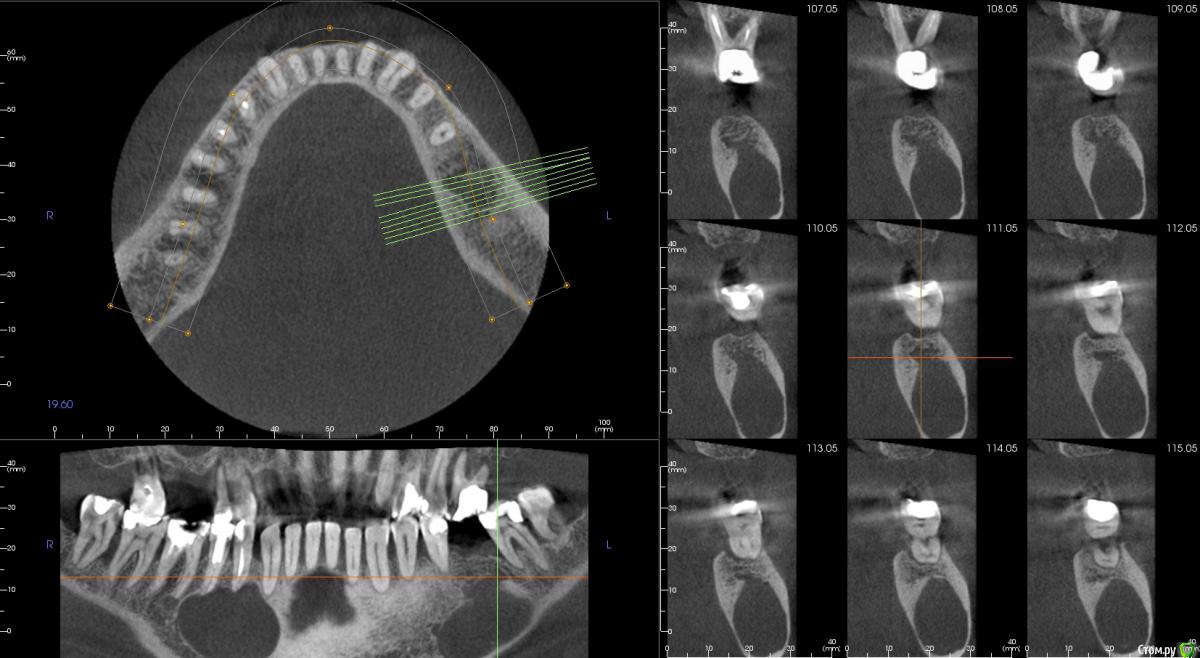

kamranchick Опубликовано 1 сентября, 2015 Поделиться Опубликовано 1 сентября, 2015 Не подскажите что с пациентом? пришел ставить мосты снизу и сверху, отправили на ОРТО, а тут такое... Ссылка на комментарий

kamranchick Опубликовано 2 сентября, 2015 Автор Поделиться Опубликовано 2 сентября, 2015 Артефакт наверное)сначала прицельный сделали, потом панорамный, потом на кт, везде одна и та же картина была Ссылка на комментарий

JDS Опубликовано 2 сентября, 2015 Поделиться Опубликовано 2 сентября, 2015 А может обширная генерализованная радикулярная киста?? Слева будто резидуальная. Не буду тыкать в небо, дождемся ответа опытных))) Ссылка на комментарий

pigmaleon Опубликовано 2 сентября, 2015 Поделиться Опубликовано 2 сентября, 2015 Радикулярная и резидуальная кисты. 1 Ссылка на комментарий

major Опубликовано 2 сентября, 2015 Поделиться Опубликовано 2 сентября, 2015 В ЧЛХ. Там ребята если не будут подстраховываться(биопсия и т.д.) прооперируют с формированием дефекта или без. Скорее всего остеосинтез пластинами планироваться будет возможно + костные блоки из гребня подвздошной. Возможен дистракционный остеогенез, если будет дефект. Заинтересованные зубы удаляются.Онконастороженность никто не отменял))) Материал на гистологию конечно же. Ссылка на комментарий